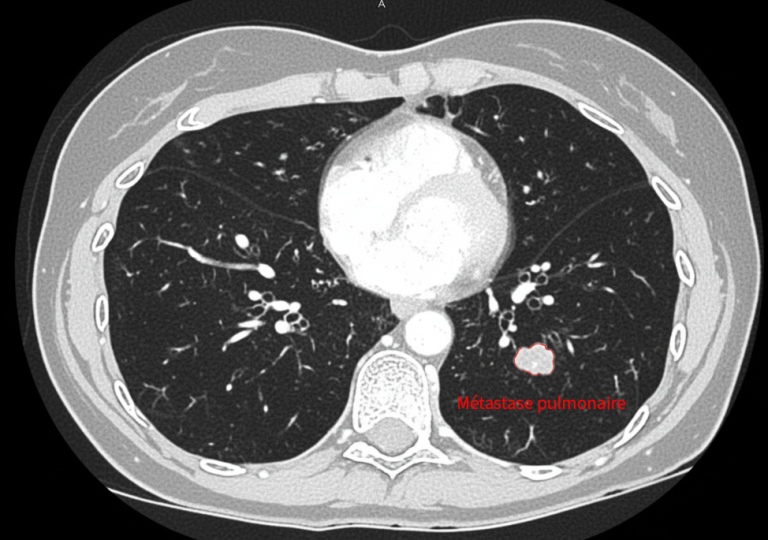

Cas clinique : une prise en charge personnalisée et combinée

L’exemple de Mme F., 50 ans, illustre parfaitement l’intérêt de ces techniques.

Suivie pour un cancer colorectal métastatique, elle présente une nouvelle récidive avec :

• une métastase pulmonaire de 2,5 cm, située près de structures centrales,

• une métastase hépatique de 1 cm, profonde et difficilement accessible chirurgicalement.

Traitement pulmonaire par cryoablation

La lésion pulmonaire est traitée par cryothérapie, permettant une destruction efficace tout en évitant une chirurgie lourde (lobectomie).

Un pneumothorax, complication attendue, est pris en charge simplement avec un drain temporaire.

En images

Images du traitement des organes (poumon et foie) avant, pendant et après le traitement.